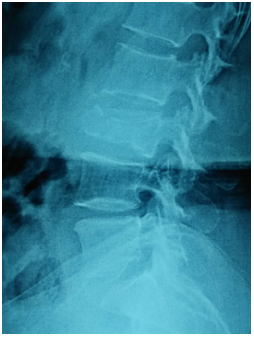

(上圖為患者術(shù)前X片)